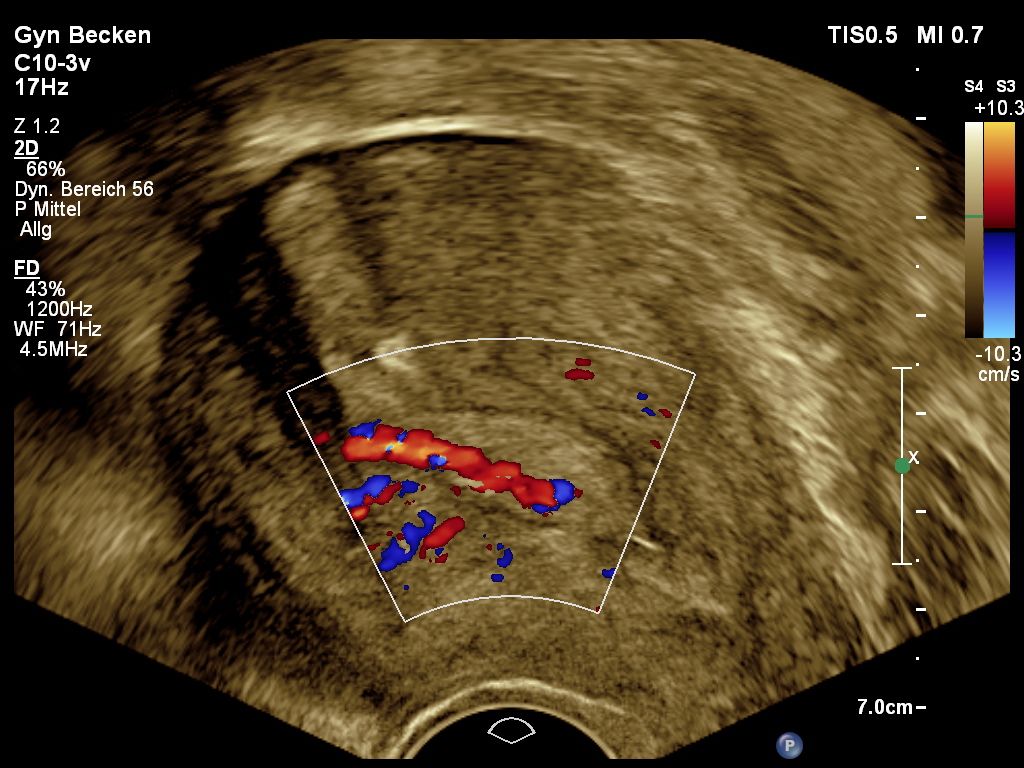

Ovarialkarzinom

Veränderungen des Eierstocks sind gerade vor den Wechseljahren häufig funktioneller Natur und durch zyklusbedingte Einflüsse zu erklären. Diese sollten nicht beunruhigen und sind in aller Regel im natürlichen Verlauf abzuwarten. Raumforderungen am Eierstock können aber auch Beschwerden hervorrufen. Zum anderen sollten sie gegen bösartige Veränderungen abgegrenzt werden. Letztere sind selten, jedoch von ungünstiger Prognose, wenn sie ein fortgeschrittenes Stadium erreicht haben.

Die Abgrenzung zwischen einer einfachen funktionellen Veränderung, einer gutartigen Veränderung oder einer potentiell bösartigen Veränderung sollte primär sonographisch erfolgen.